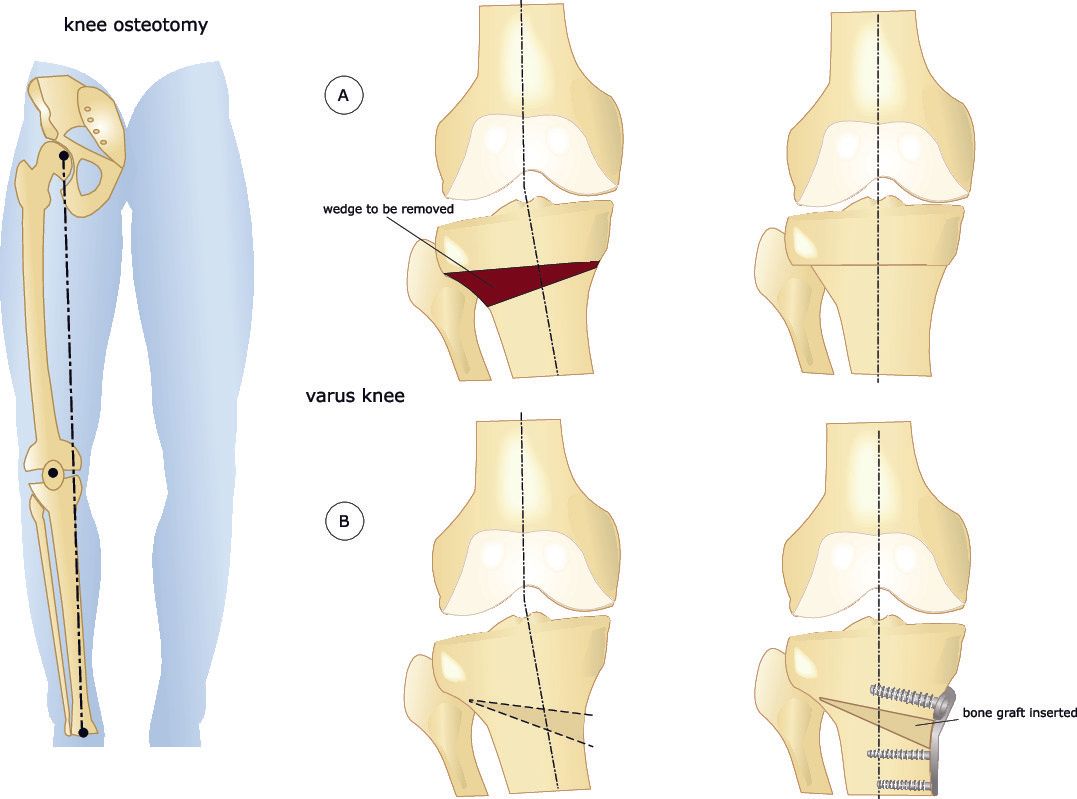

- High Tibial Osteotomy (HTO):

- This involves cutting the tibia (shin bone) close to the knee but not affecting the knee joint surface

- Realigning the tibia and holding it in place with metalwork

- This is most commonly performed for varus knees

- Both the high tibial and the distal femoral osteotomies can be performed:

- Opening wedge:

- This involves making a single cut in the bone and opening up the gap

- Closing wedge:

- This involves making two cuts to the bone that converge together in order to remove a wedge of bone

- The gap is then closed by bending the bone at the small

- A varus knee deformity can be corrected with a medial opening wedge osteotomy (more common) or a lateral closing wedge osteotomy of the proximal (upper) tibia

- In an open wedge osteotomy a clamp is placed within the bone cut and the gap opened to the desired amount

- Depending on the size of the gap bone graft may be used to fill the gap

- In a closed wedge osteotomy two bone cuts are made to the bone (instead of one) so that a wedge of bone can be removed and then the bone realigned to close the gap and the bone ends to touch

- With both open and closing wedge osteotomies the osteotomy is secured with metalwork which is typically a plate and screws